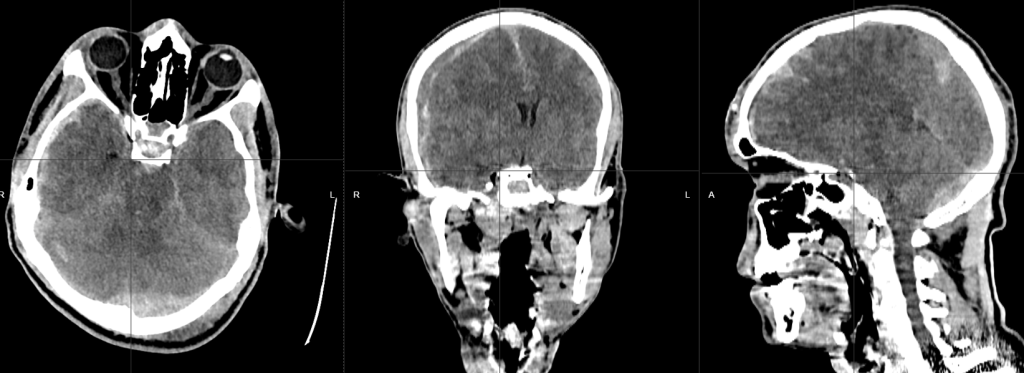

Paciente de 21 años, masculino, con historia de trauma craneal por accidente vial en motocicleta; con importante deterioro neurológico; al analizar la tomografía cerebral; se identifica hematoma epidural en fosa posterior izquierda, asociada con trazo de fractura; además hay hematoma subdural en hemisferio cerebral derecho, aumento de la densidad de los surcos y cisuras en relación con hemorragia subaracnoidea postraumática, y datos de edema cerebral difuso postraumático.